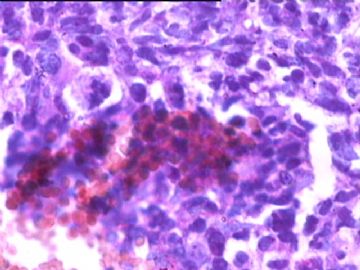

女,34y,头痛一月,右额叶占位:5*5*4cm。囊性区域,4cm。大体:3.5x3x1cm灰白间暗褐色组织一堆,质嫩。临床诊断1:胶质瘤,2:血管母细胞瘤。

本人县级医院头颅手术少,考虑胶质母细胞瘤。大家指导指导。

同意胶质母细胞瘤。细胞异型、坏死、核分裂、血管内皮肿胀增生均可见到。

This is certainly a WHO grade IV malignant neoplasm. While most likely a glioblastoma, I would carefully rule out PNET by staining for GFAP and neuronal markers such as synaptophysin, NeuN and NSE. Rarely, PNET may shows marked pleomorphism and indistinguishable from glioblastoma on HE stain.

同意马老师的意见,该肿瘤从形态及年龄来看考虑PNET或GBM,须标记Syn、NSE、S-100、NeuN和GFAP来鉴别。

结合图片细胞形态特点考虑胶质母细胞瘤,组化标记排除其他